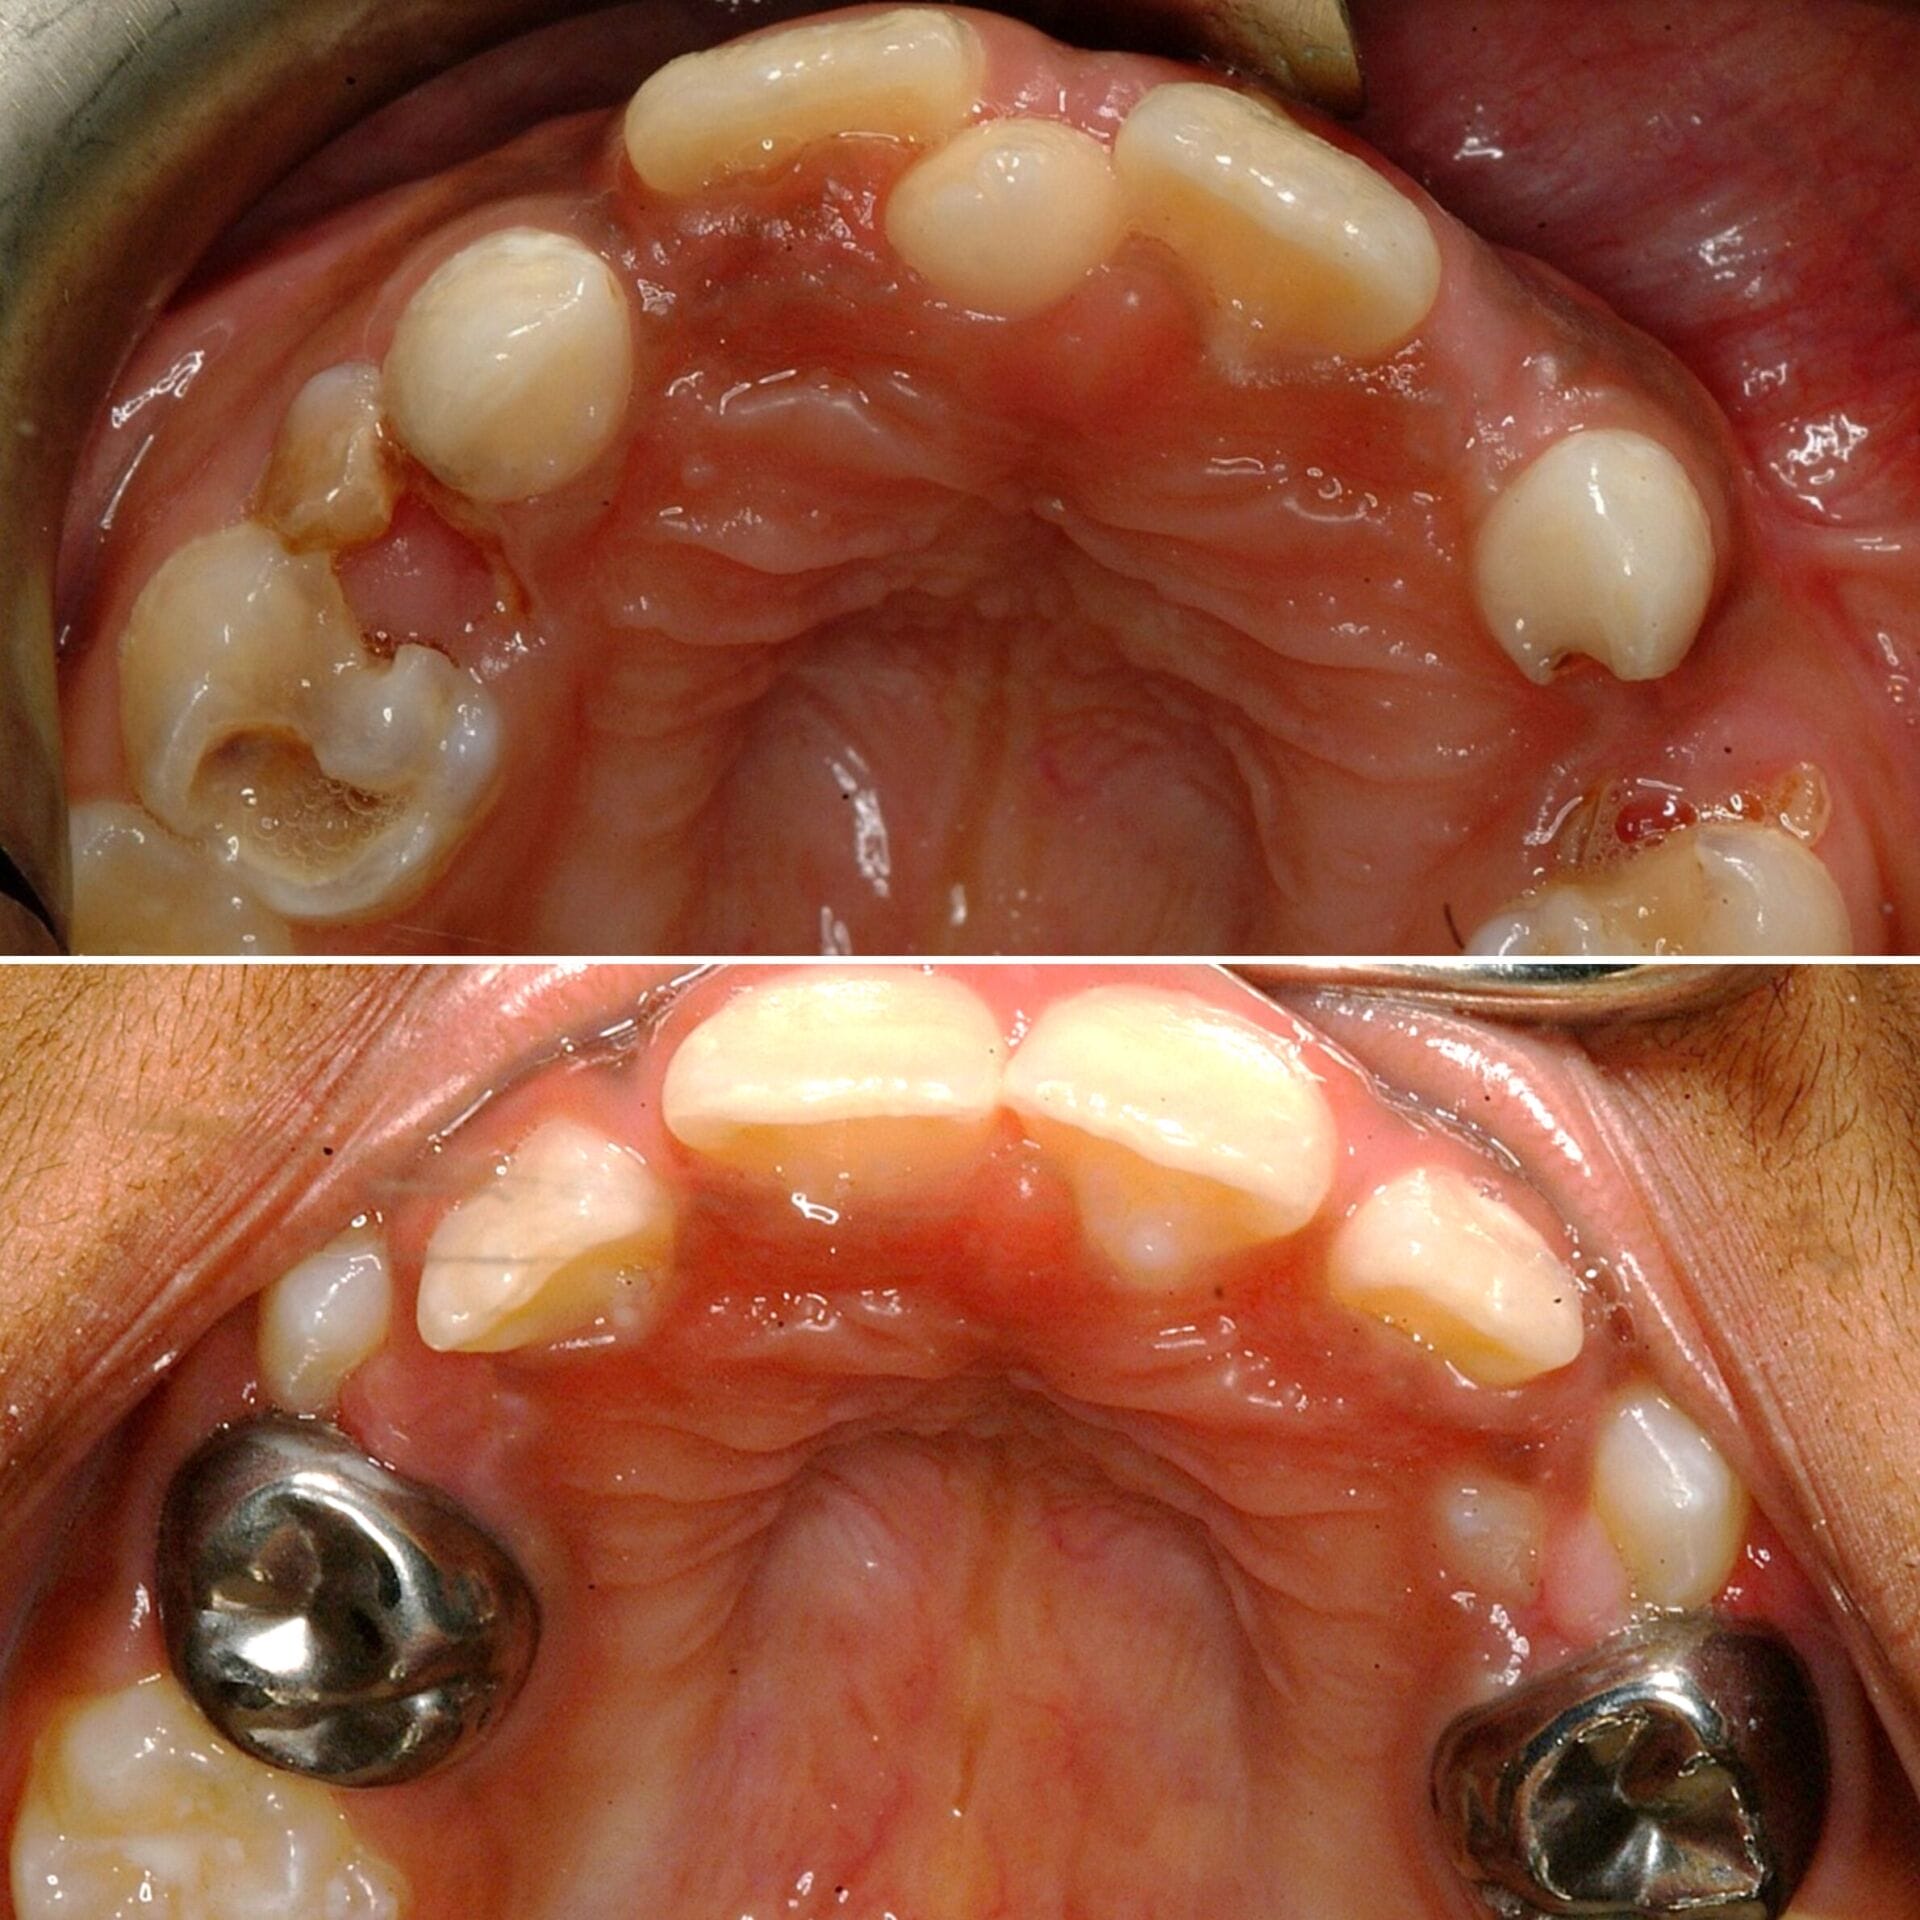

- Have complex or multiple dental issues requiring longer procedures

- Require full-mouth rehabilitation or extensive extractions